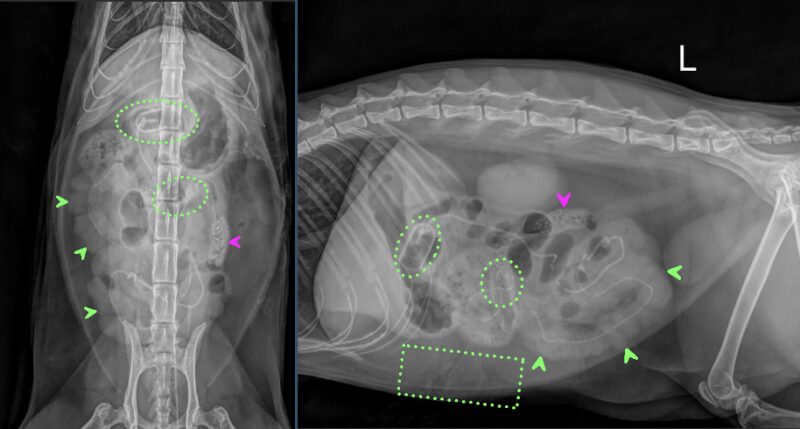

Liebe Kolleg:innen, vielen Dank für das Zusenden der Röntgenaufnahmen der Katze Bonita. In den vorliegenden dextro-sinistralen sowie ventro-dorsalen abdominalen Röntgenbildern zeigen sich mehrere auffällige Veränderungen im Bereich des Magen-Darm-Trakts. Auf Höhe des Übergangs von Pylorus zu proximalen Duodenum ist eine ovoide Struktur mit mineraldichtem peripherem Saum erkennbar, die zu einer mechanischen luminalen Einengung in diesem Bereich führt (erste grün gepunktete Kreise). Ausgehend von dieser Struktur projiziert sich ein lineares, röntgendichtes Material innerhalb des gesamten Dünndarms, wodurch es zu einer markanten Auffädelung mehrerer jejunaler Darmabschnitte kommt (grüne Pfeilköpfe). Eine weitere ähnlich ovale röntgendichte Struktur befindet sich innerhalb des Jejunums, die eine zusätzliche mechanische Obstruktion verursacht (zweite grün gepunktete Kreise). Es bestehen innerhalb des gastrointestinalen Trakts multifokale Gasblasen, die von weichteildichtem Darminhalt umgeben sind. Das fadenförmige Fremdmaterial endet auf Höhe des Colon descendens in einer kotähnlichen Formation (pinker Pfeilkopf). Aborad dieser Struktur stellt sich das restliche Colon leer dar.

Der Magen ist zusätzlich leicht bis moderat Gas gefüllt. Es besteht kein Hinweis auf freie Flüssigkeit oder freies Gas innerhalb der Peritonealhöhle. Die Leber stellt sich spitzrandig und gut abgrenzbar dar. Milz, Nieren sowie die Harnblase sind ohne besonderen Befund. Im ventralen Anteil des Abdomens ist in der seitlichen Projektion ein Artefakt erkennbar, sehr wahrscheinlich bedingt durch Ultraschallgel des zuvor durchgeführten A-FASTs (grüner gepunkteter Quadrant), welches somit als nicht pathologisch zu bewerten ist. Zudem besteht intraabdominal ein deutlicher Anteil an fettdichter Verschattung. Der abgebildete Bewegungsapparat ist unauffällig.

Zusammenfassend ist von einem mechanischen Ileus auszugehen, verursacht durch röntgendichtes Fremdmaterial im Bereich des Pylorus/proximalen Duodenums sowie des Jejunums. Zusätzlich befindet sich ein linearer Fremdkörper innerhalb des Dünndarms, der zu einer Auffädelung multipler Dünndarmschlingen führt, derzeitig ohne Hinweis auf Perforation. Es besteht jedoch ein erhebliches Risiko für Strangulation, Ischämie und Darmperforation, womit es sich hierbei um einen chirurgischen Notfall handelt und dringend zu einer zeitnahen operativen Versorgung geraten wird.